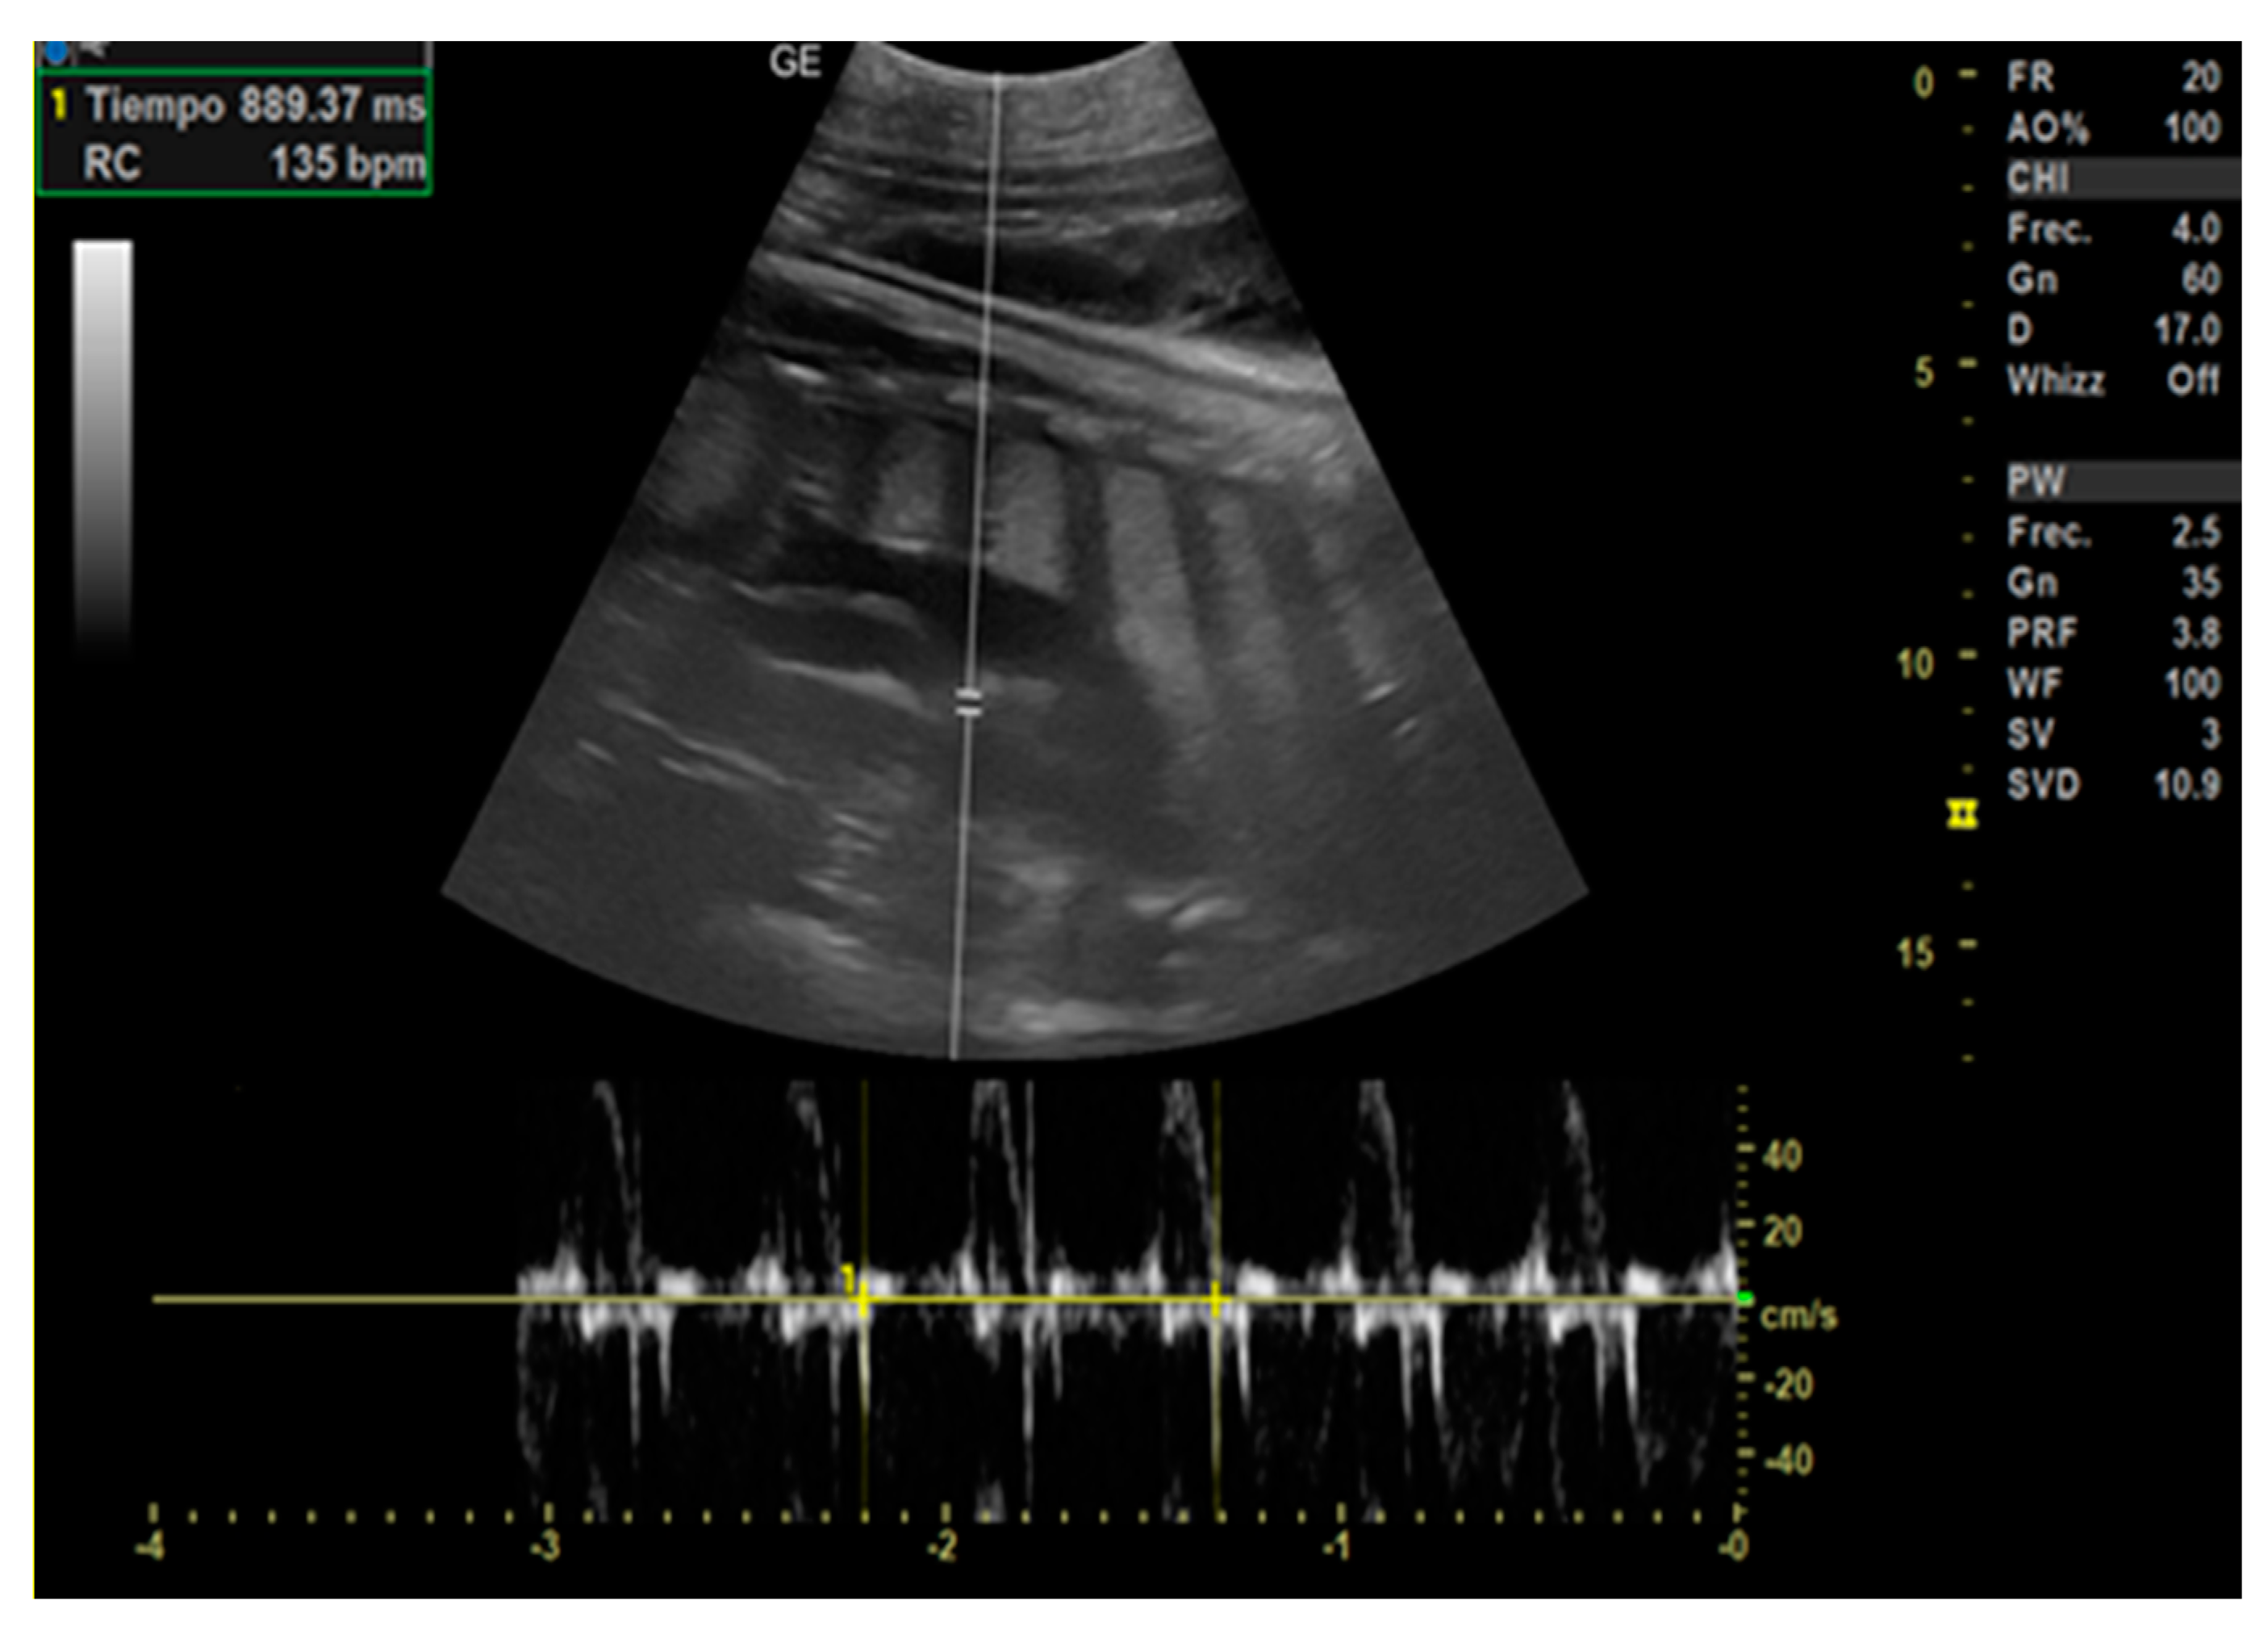

- Day 129 ± 3: Embryonic cardiac mechanics is displayed, as a point of maximum fluctuation of the echoes. It is possible to recognize from the beginning of the heart rate. The heart rate was measured once the cardiac mechanics became visible and remained constant between 205 and 155 bpm until the ninth month of pregnancy. For the next 3 months, it stabilized at 140–135 bpm (Figure 3).